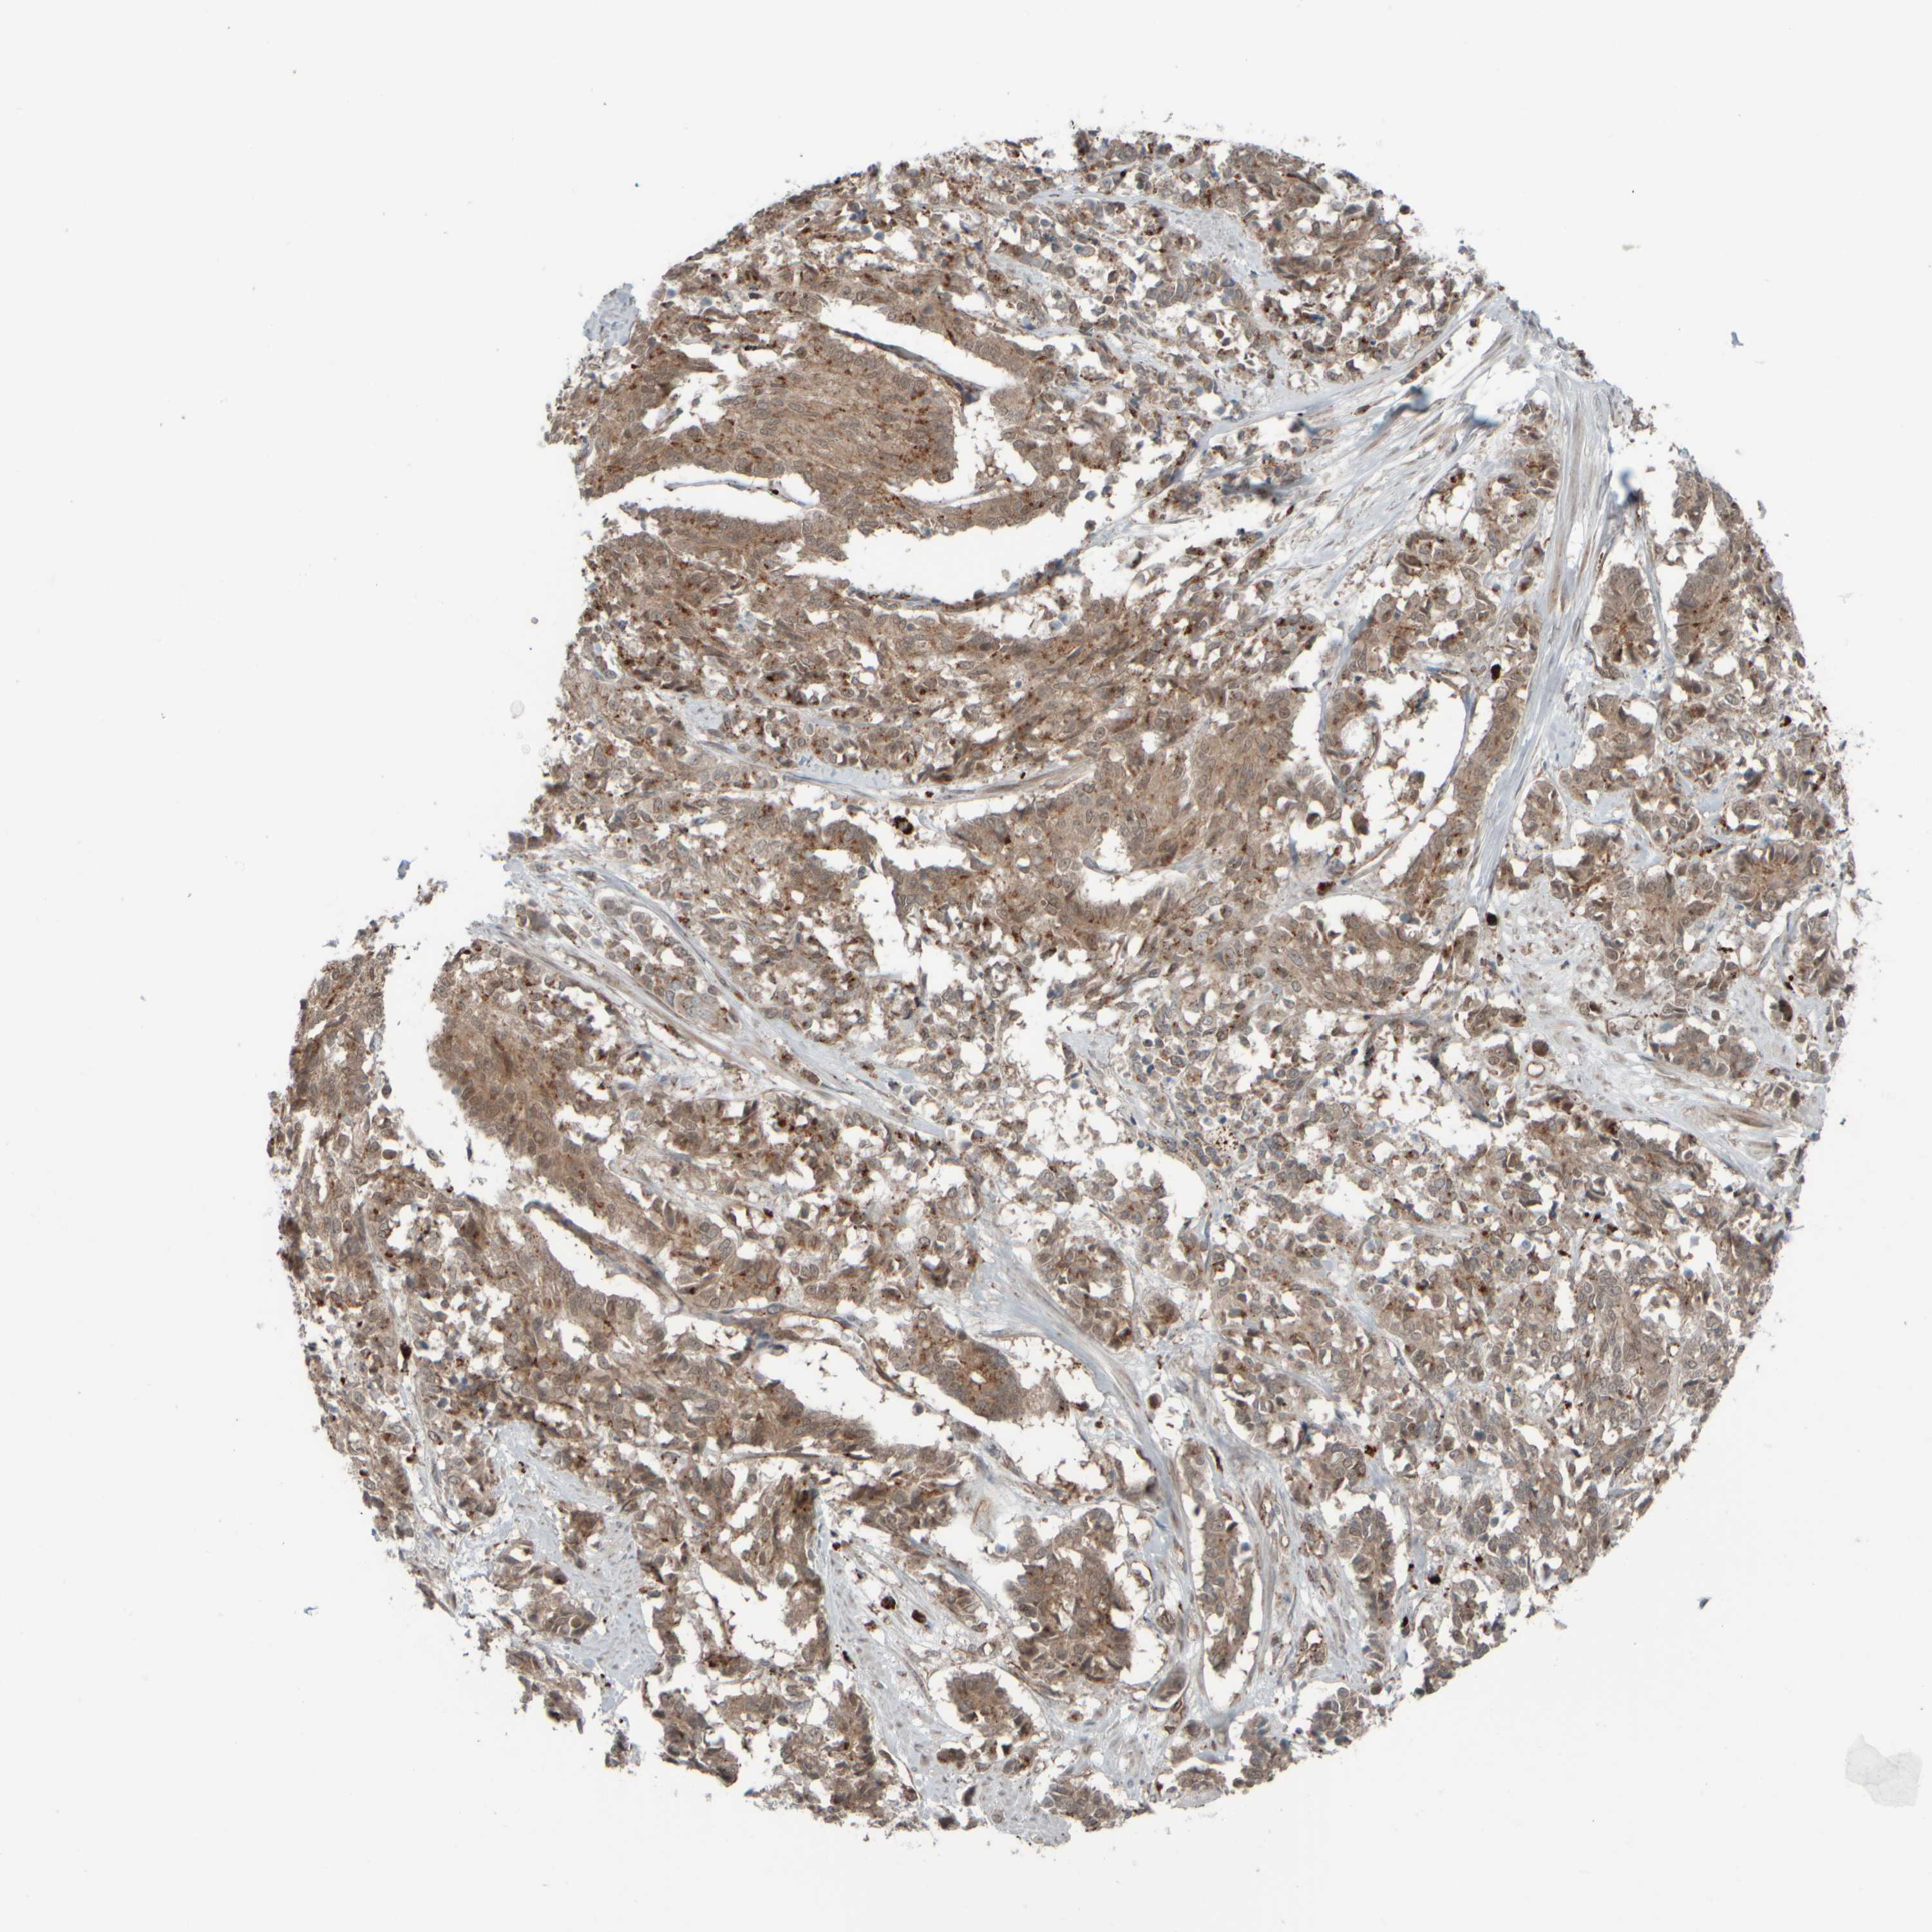

CERVICAL CANCER - Protein expressioni

A mouse-over function shows sample information and annotation data. Click on an image to view it in a full screen mode. Samples can be filtered based on level of antibody staining by selecting one or several of the following categories: high, medium, low and not detected. The assay and annotation is described here.

Note that samples used for immunohistochemistry by the Human Protein Atlas do not correspond to samples in the TCGA dataset.

Antibody stainingi

Antibody staining in the annotated cell types in the current human tissue is reported as not detected, low, medium, or high, based on conventional immunohistochemistry profiling in selected tissues. This score is based on the combination of the staining intensity and fraction of stained cells.

Each image is clickable and will lead to virtual microscopy that enables deeper exploration of all samples and also displays staining intensity scores, fraction scores and subcellular localization as well as patient and tissue information for each sample.

Antibody HPA020999

Antibody HPA023995

Staining

High

Medium

Low

Not detected

Intensity

Strong

Moderate

Weak

Negative

Quantity

>75%

75%-25%

<25%

None

Location

Nuclear

Cytoplasmic/membranous

Cytoplasmic/membranous,nuclear

Squamous cell carcinoma, NOS

Adenocarcinoma, NOS